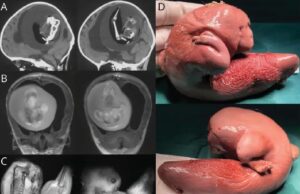

Νέο δρόμο κατά του καρκίνου του παγκρέατος δείχνει φάρμακο για τη...

Ένα παλιό φάρμακο για την καρδιά διαπιστώθηκε ότι μπορεί να αναστείλει μια από τις πιο κοινές και θανατηφόρες μορφές καρκίνου του παγκρέατος, τουλάχιστον σε πειραματόζωα.

Σε μια μελέτη...